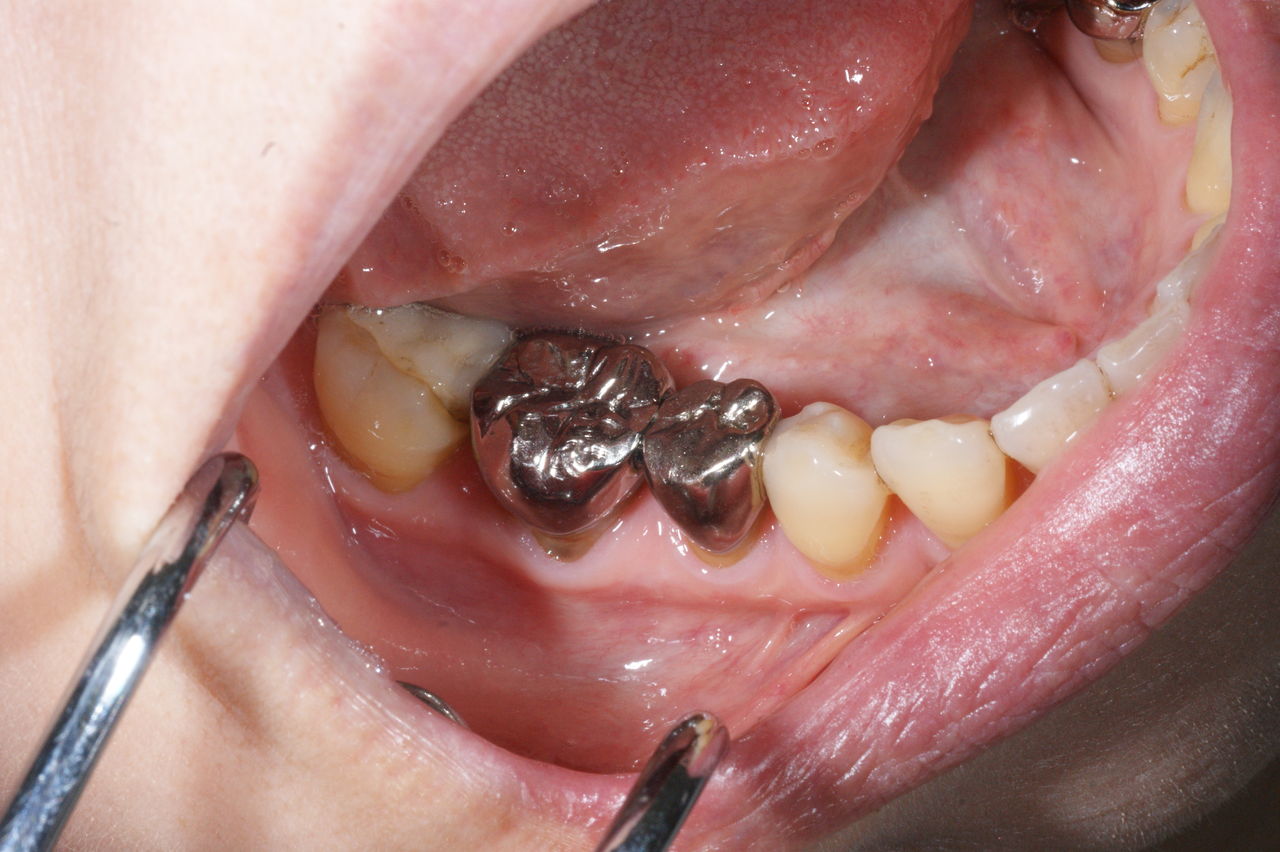

425.審美性 2019年06月21日 14:51 開口時、真っ先に金属歯が眼に入ります。 人工的な装着物が入っているのに、それを感じさせず、未治療の歯と調和して、自然に見えること。それが審美の審美たる所以ではないでしょうか!?(大) 「審美治療」カテゴリの最新記事 「修復治療」カテゴリの最新記事 < 前の記事次の記事 > コメント コメントフォーム 名前 コメント 評価する リセット リセット 顔 星 投稿する 情報を記憶